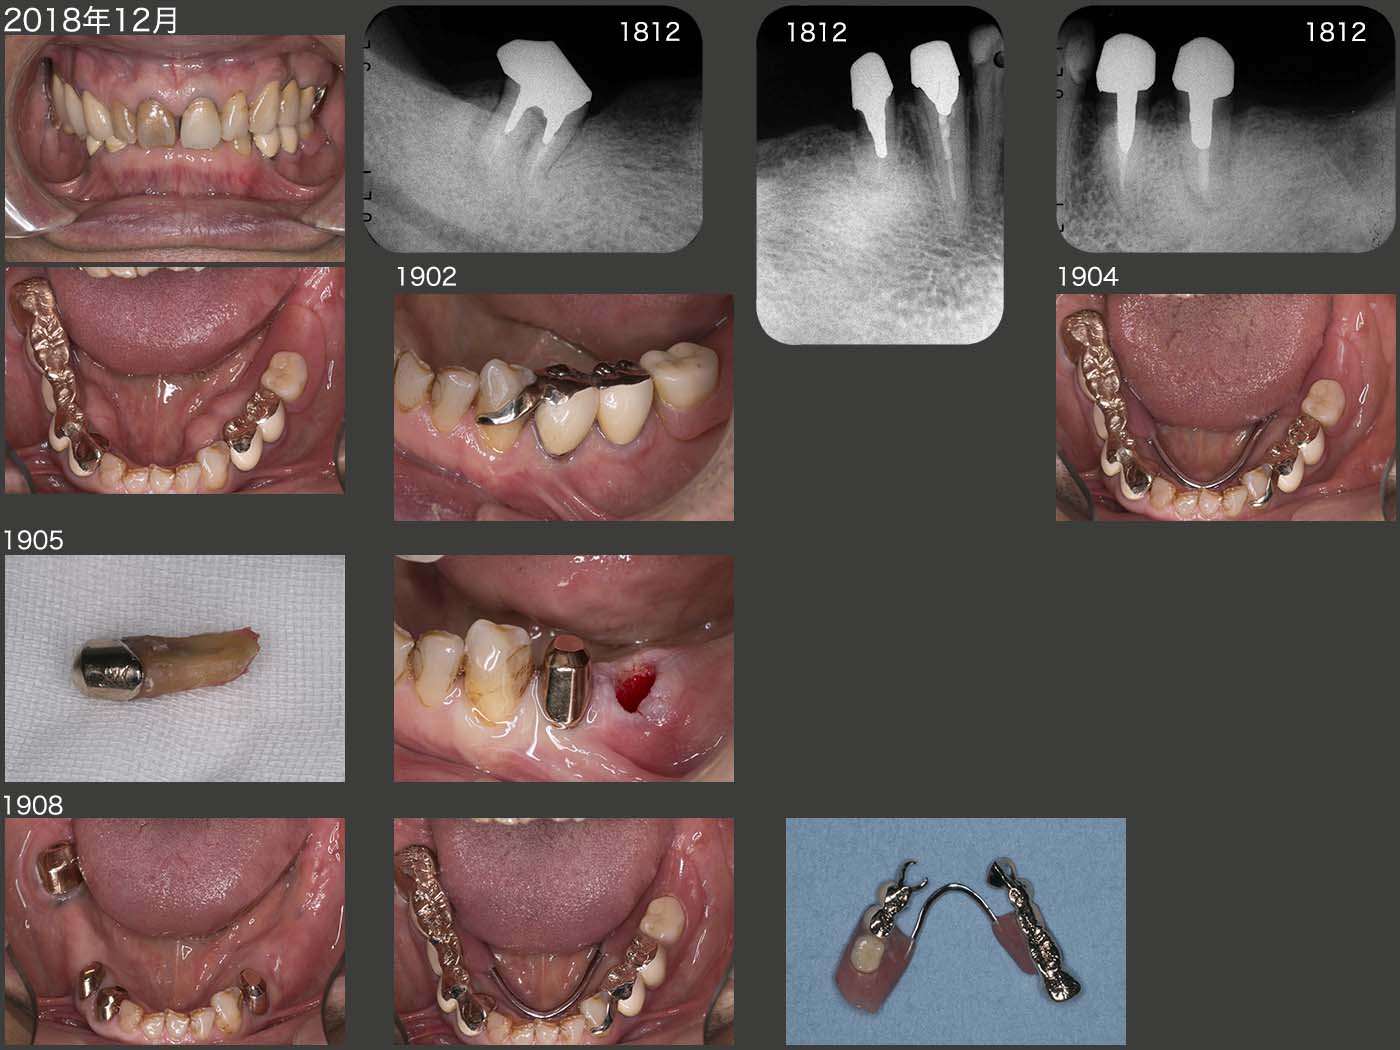

7.症例7

私が歯科医師になって2年目に治療した患者さん.1981年に右下ブリッジを自分で技工を行い,装着した.いわゆるロング・スパン・ブリッジである.暫くお目にかからなかったが,私が歯科医院を開業したのを機に,14年振りに95年11月に来院した.(中段パノラマX線写真)

2005年に左下7を歯根破折で失ったが,義歯を装着しないまま経過した.スライド下段は10年10月の状態.

2011年8月,歯根破折が原因で左上4を抜去し,12年2月に③4⑤のブリッジを装着した.ここで,左側大臼歯部でも咀嚼してもらいたいため,12年10月,左下にコーヌス義歯を装着した.(スライド上段)

この患者さんの習慣性咀嚼側は左側と思われる.だからこそ右下のロング・スパン・ブリッジが30年以上保ったといえる.さらに,ブリッジのポンティックを極端に小さくしたことが,左側咬みを助長したと思われる.13年7月,右下ブリッジのマージン部にう蝕がみられたのを機に,作り直しに同意していただいた.14年,右下に,可撤式ブリッジ(コーヌス義歯)を装着した.

この症例のようなロング・スパン・ブリッジにおいて,ポンティックの大きさを普通に作れば,ブリッジの支台歯の荷重負担に繋がるし,逆に小さく作れば反対側の歯の負担を助長する.バランスがとれた大きさにするのは難しいと痛感すると同時に,その際は咬合力の大きさ,有髄か否か,咀嚼側の見極め等,よく考えて製作することが重要である.

その後,2018年5月に左下5に6mm歯周ポケットが急に生じたため,歯根破折と診断した.しかし自覚症状がなく,患者さんの希望で暫く経過をみることとなった.12月,左側で咬みづらくなり,右側ばかりで嚙んでいるためか,デンタルX線写真より右下7の歯根膜空隙の拡大がみられた.歯周ポケットは問題ないが,このまま右側咬みが続くと,右下7も歯根破折する可能性が高いと判断し,治療に介入させて頂くことになった.まず,19年2月,左下3のクラスプを製作し,左下コーヌス義歯と溶接した.また,今回両側性設計の義歯に移行するために,3月に下顎隆起の除去を2回に分けて行った.4月に,リンガルバーを追加した.5月に満を持して左下5を抜去した.

左下3は有髄歯であるからまず心配ないが,右下3が無髄歯であるから,何とか右下7および4が防波堤となり,右下3の喪失に繋がらないように願っている.